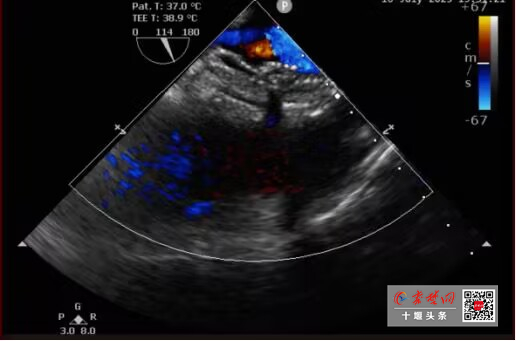

• 全國首例!十堰人醫(yī)“雙降解”封堵術(shù)巧補(bǔ)心臟雙“洞”不留痕

全國首例!十堰人醫(yī)“雙降解”封堵術(shù)巧補(bǔ)心臟雙“洞”不留痕

近日,十堰市人民醫(yī)院心臟中心實現(xiàn)重大突破,成功為一名27歲雙孔型房間隔缺損(ASD)患者植入全國首例雙生物可降解封堵器。這項高難度手術(shù)的圓滿成功,不僅完美修復(fù)了患者的心臟,更標(biāo)志著繼可降解單孔房缺封堵術(shù)、可降解卵圓孔未閉封…

今日房縣網(wǎng)訊?通訊員 秦洪濤? 馬婷婷 沈俊 報道:近日,十堰市人民醫(yī)院心臟中心實現(xiàn)重大突破,成功為一名27歲雙孔型房間隔缺損(ASD)患者植入全國首例雙生物可降解封堵器。這項高難度手術(shù)的圓滿成功,不僅完美修復(fù)了患者的心臟,更…